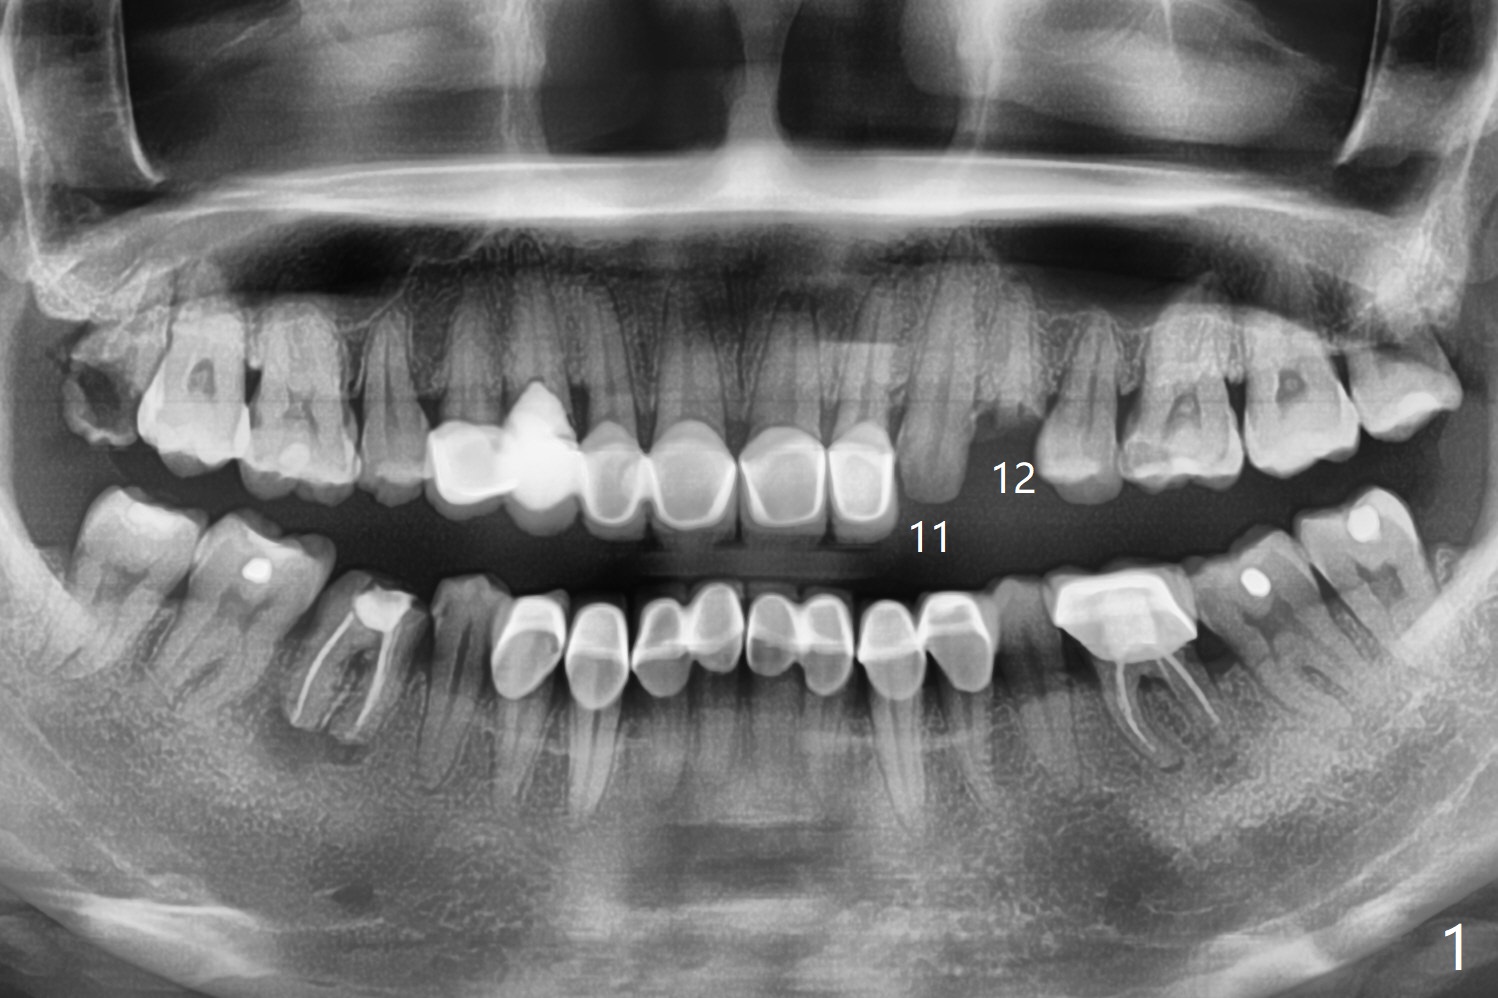

A 44-year-old woman has multiple restoration, partially related to Tetracycline teeth (Fig.1). Splinted crowns at #11 and 12 have dislodged. Since the bone height is limited, a 4x11.5 mm IS implant with high stability will be chosen. The immediate provisional will be splinted.